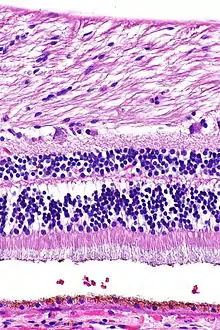

H&E is the combination of two histological stains: hematoxylin and eosin. The hematoxylin stains cell nuclei a purplish blue, and eosin stains the extracellular matrix and cytoplasm pink, with other structures taking on different shades, hues, and combinations of these colors.[5][6] Hence a pathologist can easily differentiate between the nuclear and cytoplasmic parts of a cell, and additionally, the overall patterns of coloration from the stain show the general layout and distribution of cells and provides a general overview of a tissue sample's structure.[7] Thus, pattern recognition, both by expert humans themselves and by software that aids those experts (in digital pathology), provides histologic information.

Hematoxylin principally colors the nuclei of cells blue or dark-purple,[6][15][14] along with a few other tissues, such as keratohyalin granules and calcified material. Eosin stains the cytoplasm and some other structures including extracellular matrix such as collagen[5][7][14] in up to five shades of pink.[8] The eosinophilic (substances that are stained by eosin)[5] structures are generally composed of intracellular or extracellular proteins. The Lewy bodies and Mallory bodies are examples of eosinophilic structures. Most of the cytoplasm is eosinophilic and is rendered pink.[10][15] Red blood cells are stained intensely red.

Muscle tissue, cell nuclei (blue-purple), cell body (pink).

Basal cell carcinoma of the skin, cell nuclei (blue-purple), extracellular material (pink).